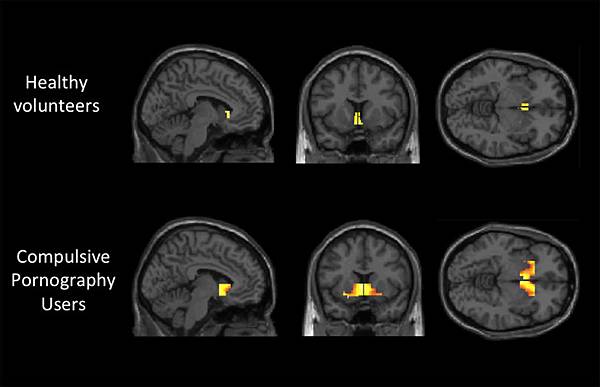

*健康大腦 vs. 長期使用色情的大腦